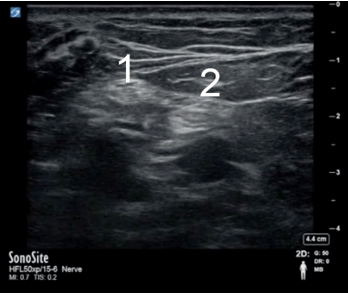

Popliteal 2 Image

Common Peroneal Nerve

Tibial Nerve